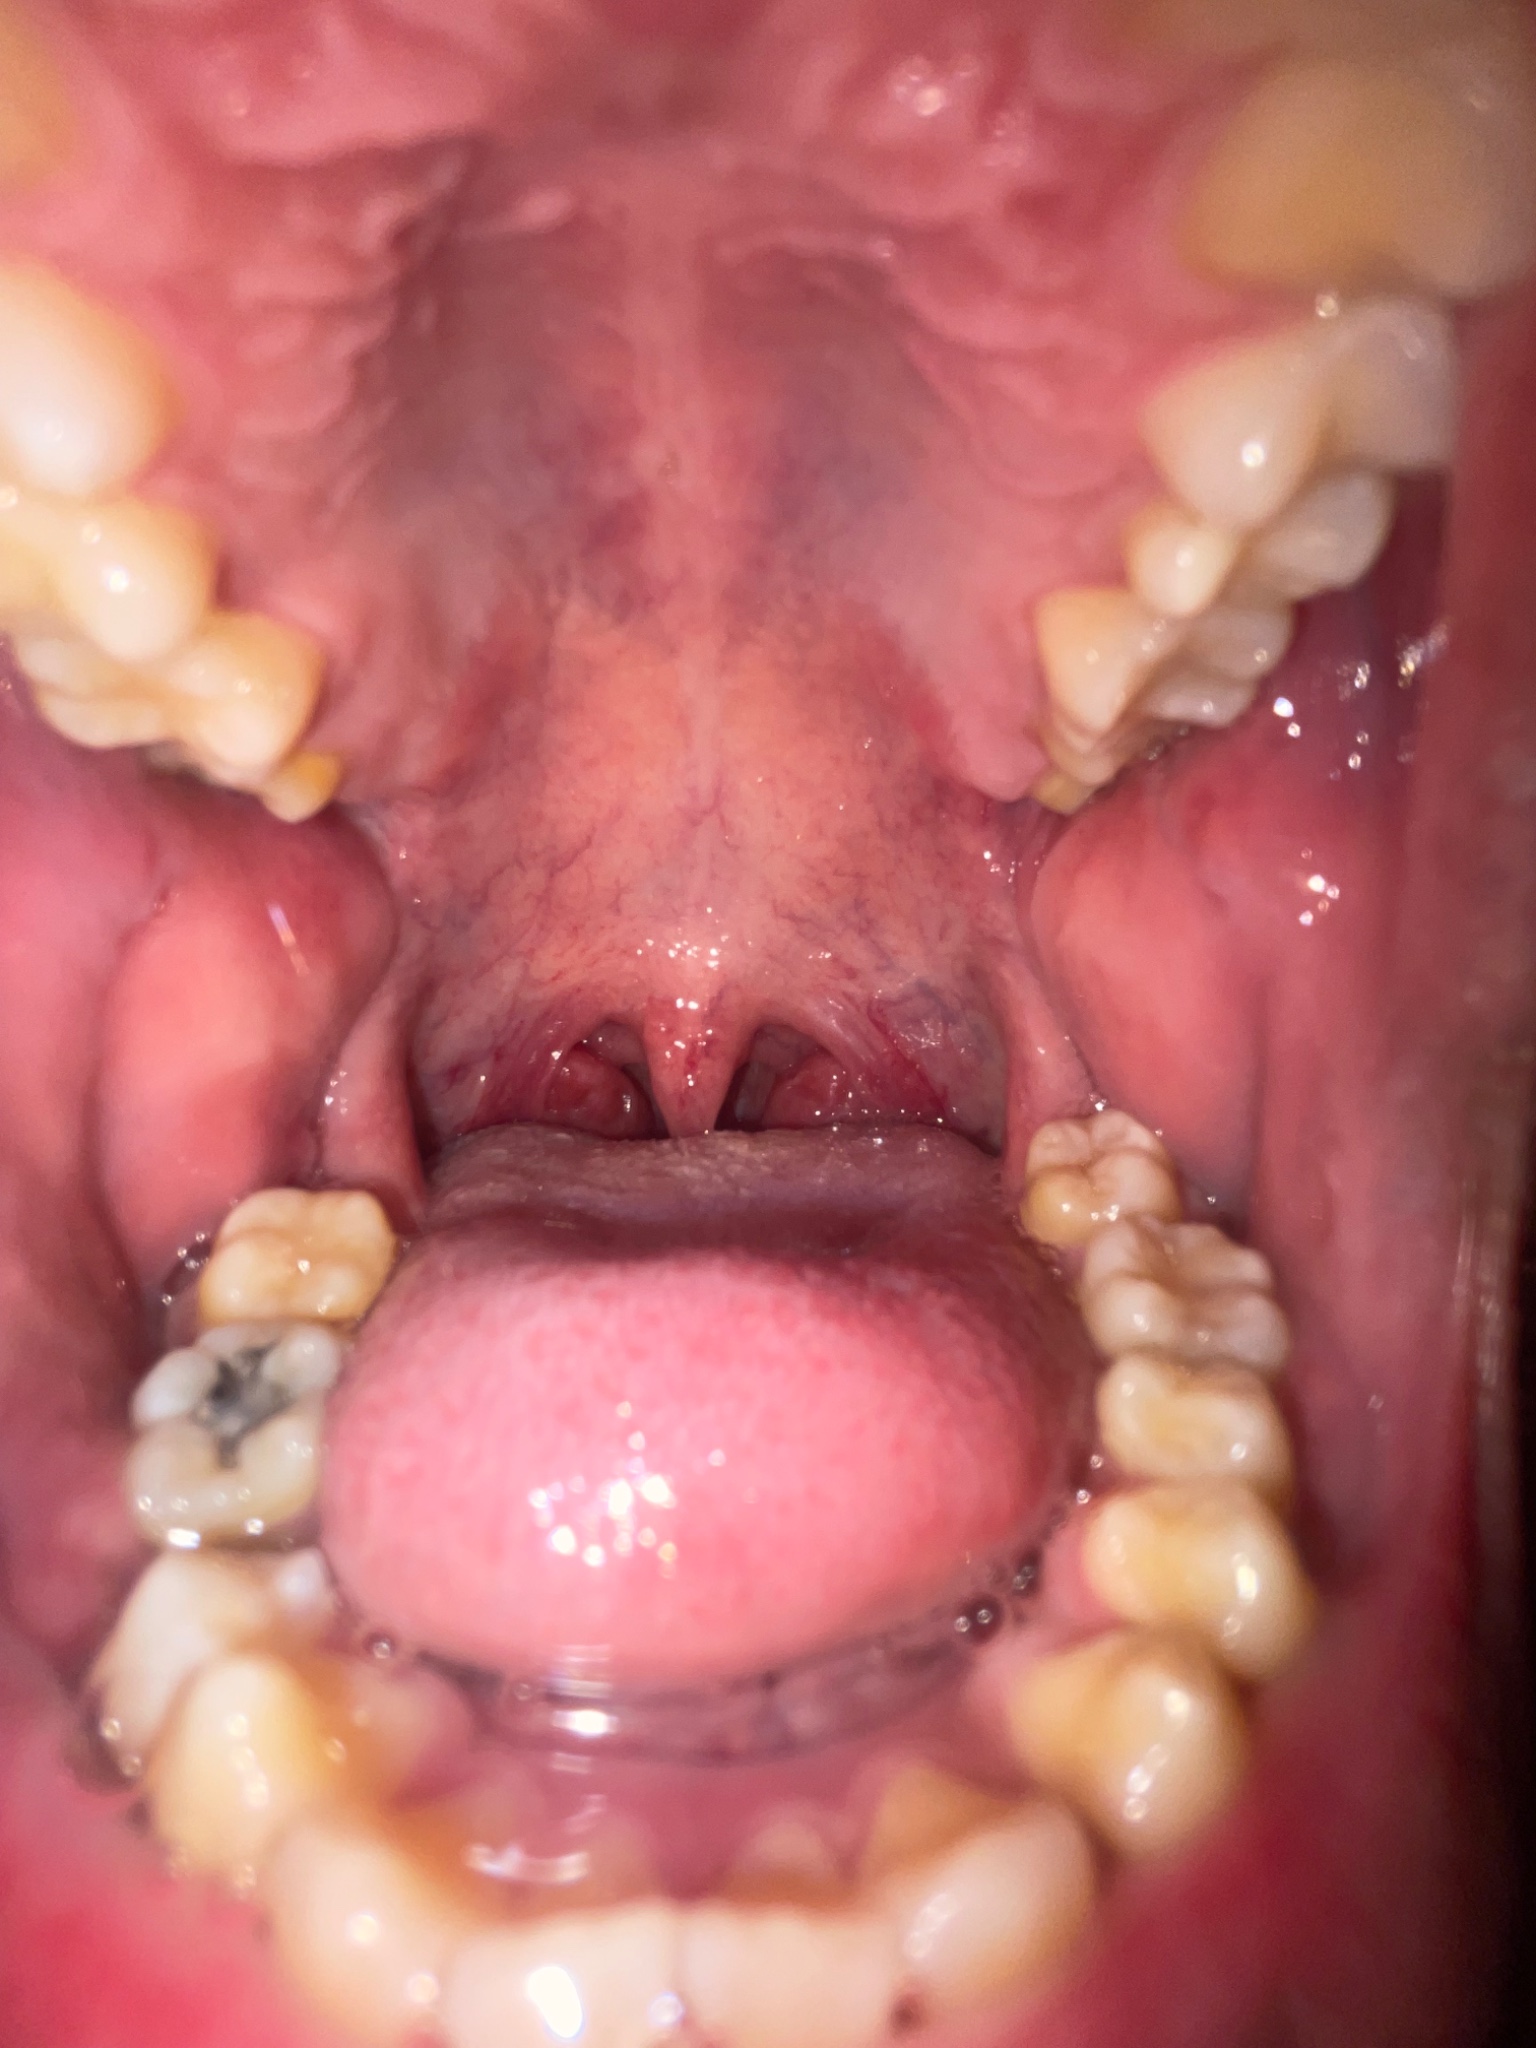

ผมเป็นตุ่มใส่ๆตรงลิ้นไก่นะครับ มันอันตรายมั้ย สอบถามผู้รู้หน่อยครับ( มีรูป )